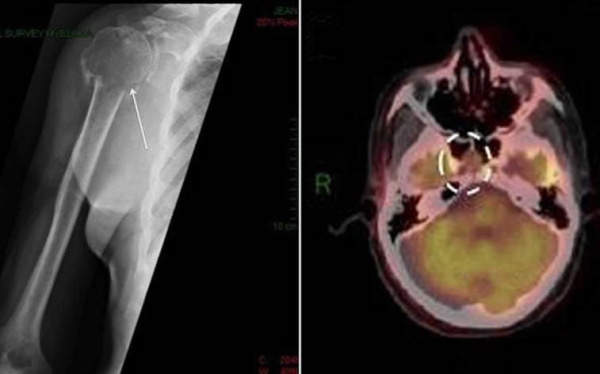

(а) Пациент с множественной миеломой (ММ). При нативной КТ в ребрах слева определяют ся множественные литические патологические участки с наличием мягкотканного компонента. При ММ обычно поражаются кости, в которых активно протекает гемопоэз, в том числе кости грудной клетки.

(б) Пациент с солитарной плазмоцитомой кости (СПК). При ПЭТ/КТ в правых задних отделах грудной стенки визуализируется крупное мягкотканное объемное образование, интенсивно поглощающее ФДГ.

ФДГ-ПЭТ/КТ позволяет определял объем поражения и эффективность лечения.